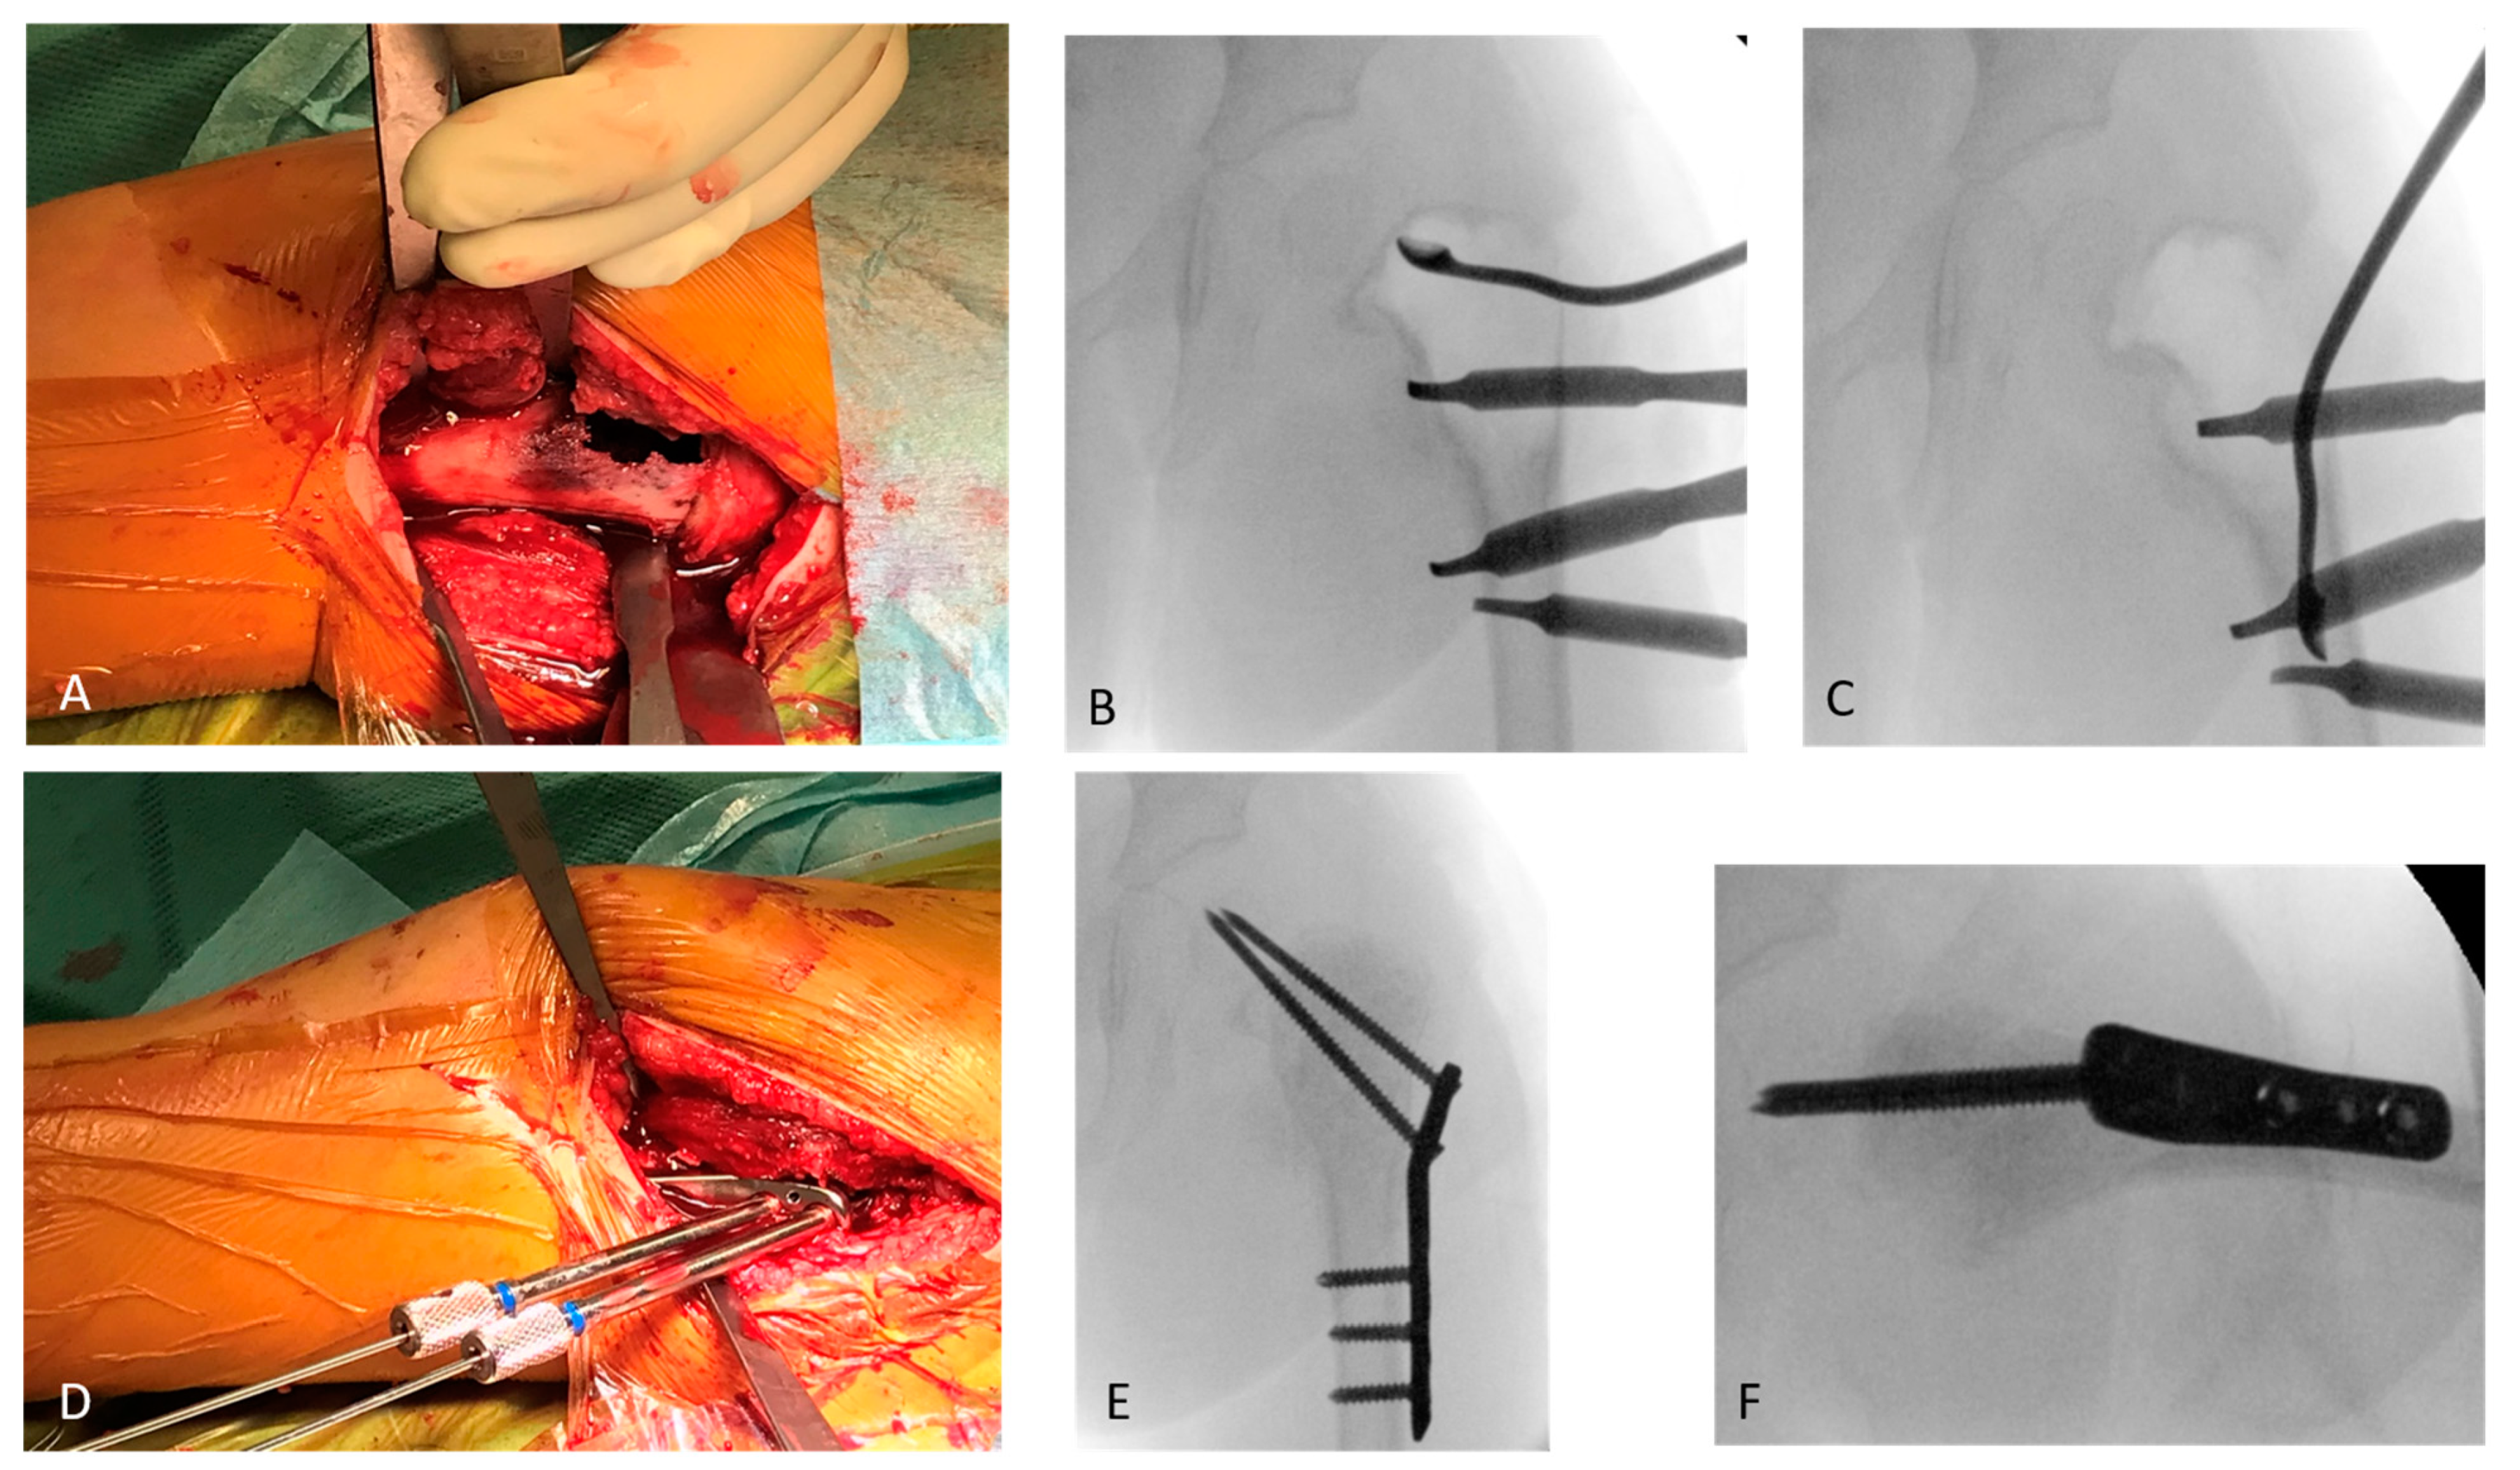

In the otherwise healthy patient, after a biopsy and an intraoperative frozen section investigation, a one-step surgical treatment was performed by subsequent curettage of the cyst (Figure 2A–C), irrigation with polidocanol, filling with allogen cancellous bone, and subsequent osteosynthesis using a locking proximal femoral plate (OrthoPediatrics PediLoc) and transphyseal locking screws (OrthoPediatrics Corp., Warsaw, IN, USA; Figure 2D–F).

Figure 2.

The femur is reached via a lateral approach. The cyst has already perforated the ventral cortex (A). The cyst is excochleated with a flexible sharp curette, which is documented with the image intensifier (B,C). After exclusion of malignancy in the frozen section and subsequent excochleation, rinsing with polidocanol and filling of the cyst with allogen spongiosa an osteosynthetic stabilisation is performed (D). After completion of the osteosynthesis, the X-ray control is carried out in two planes (E,F), showing the correct central position of the transphyseal screws in the epiphysis.